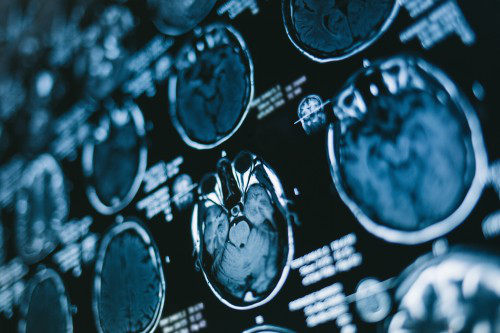

二级神经胶质瘤的治疗包括手术,放疗和化学疗法的组合,较好由多学科团队进行。手术是胶质瘤治疗优选。在多项研究中均表明了手术切除范围对预后的重要性。几项大型回顾性分析一致地证明,切除的范围与癫痫发作的独自性相关,并提高了生存率,总全切除(GTR)比近全切除和活检更有利。 但是,如果没有前瞻性研究,很难确定这是手术本身的结果还是手术是否是潜在肿瘤生物学差异的替代指标。尽管术中磁共振成像(MRI)和其他好转切除范围的技术取得了进步,但由于这些病变的浸润性,残留肿瘤几乎普遍存在,RT(放疗)和化学疗法提供了重要的辅助治疗。RT已被反复证明可以提高LGG(低级别胶质瘤)患者的生存率,并且长期以来在其治疗中起着重要作用。

在过去15年中,随着MRI用途的增加,已经发现了许多与预后不良相关的临床和影像学危险因素,包括年龄> 40岁,星形细胞瘤组织学,较大肿瘤直径> 6 cm,肿瘤越过中线和术前局灶性神经功能缺损。虽然看起来瘤种(即组织学和分子标记)和肿瘤大小都是重要的预后因素,但仍需要进一步研究以将可靠的因素纳入这些肿瘤的治疗中。